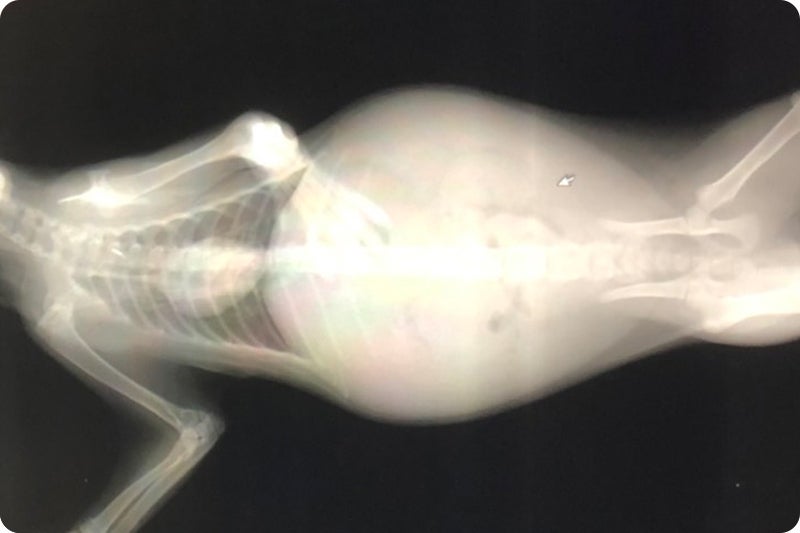

10日目になると腹水でお腹がぽっこり…歩くこともままなりません。

毎日病院で点滴を受け血液検査、レントゲン、エコー、注射を繰り返す日々。

キティの場合ウェットタイプです。

腹水が貯まりパンパンになりました。

9月7日(月) 病院Aにてレントゲン、エコー